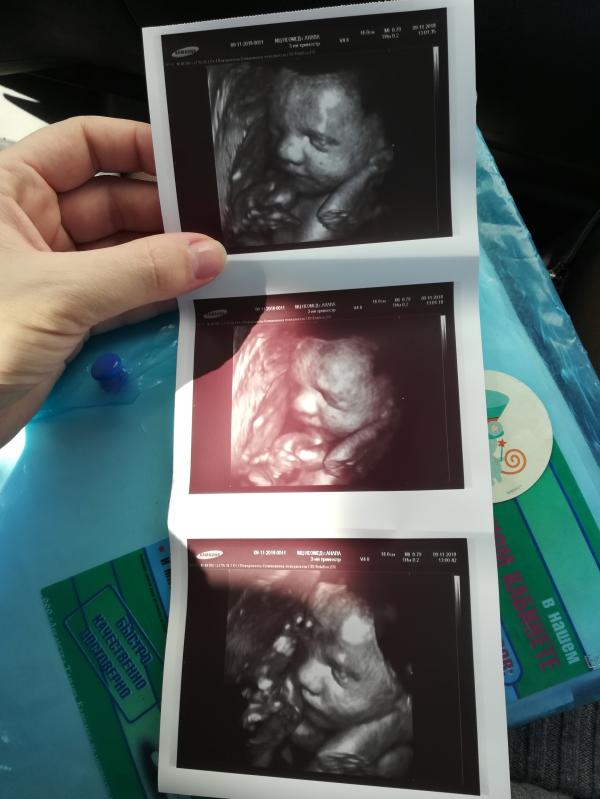

Ну что, 3ий скрининг прошёл удачно 🙏🤗. Мы ждём девочку- уже точно 😁. Все в нормах, вес уже 1400 г. 💪 Рожать, к сожалению, самой не получится, как я надеялась-рубец слишком тонкий. ( Мелкая даже улыбалась, когда её фоткали 😍Не пожалели, что поехали в Анапу к Бизикину.

4мм,после него уже другой специалист 5мм в самом тонком месте намерил.

Сколько шов намерил Бизикин? Тоже с рубцом к нему ходила, тоже скажал тонкий, он просто плохо относится к родам после кс.